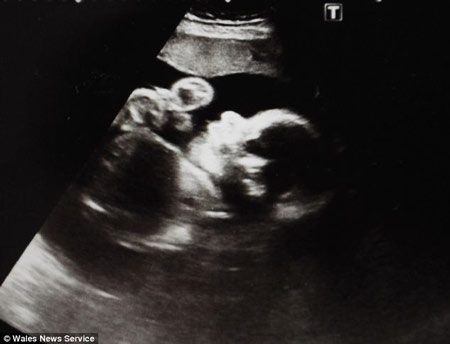

Nếu không được phẫu thuật từ trong bụng mẹ, bé Hope sẽ không thể thở được khi chào đời. Hình ảnh siêu âm của bé 5 tuần sau ca mổ.